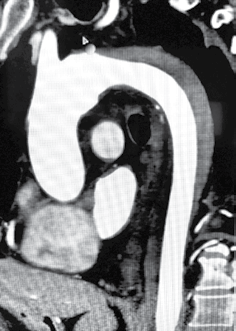

Considere o caso clínico a seguir para responder às questões de números 20 a 22.

Paciente do sexo feminino, 54 anos, portadora de hipertensão arterial sistêmica em uso de valsartana e clortalidona, hipercolesterolemia isolada sem tratamento atual, sedentarismo e obesidade grau 1. Apresenta histórico familiar de doença aterosclerótica precoce com mãe falecida aos 48 anos de infarto agudo do miocárdio. Em acompanhamento com o ginecologista, realizou a angiotomografia de artérias coronárias, apresentada a seguir, após queixa de dor torácica aos esforços maiores há 6 meses.

Sistema coronariano de dominância direita.

Tronco da Coronária Esquerda (TCE):

O TCE origina-se do seio coronariano esquerdo e trifurca.

Lesão não calcificada com estenose superior a 80% no terço distal, englobando origem da DA, Cx e ramo intermédio.

Artéria Descendente Anterior (DA):

A DA origina dois ramos diagonais e cruza o ápice do VE.

DA ocluída no óstio, englobando origem do primeiro ramo diagonal.

Artéria Circunflexa (Cx):

Cx ocluída no óstio, englobando a origem do primeiro ramo marginal.

Segundo ramo marginal apresenta lesão não calcificada com estenose superior a 80% no óstio.

Artéria Coronária Direita (CD):

A CD origina-se do seio coronariano direito e é dominante.

CD apresenta lesões parcialmente calcificadas com estenoses inferiores a 20% nos terços proximal e médio.

Ramo DP apresenta calcificações parietais sem estenoses significativas.

Ramo VP afilado e livre de lesões.

Informações Complementares:

Ausência de ateromatose nos segmentos aórticos parcialmente visualizados.

Aorta ascendente mede 25 mm ao nível do tronco pulmonar.

Pericárdio sem alterações.

CONCLUSÃO:

O escore de cálcio é superior ao percentil 75 para idade e sexo.

A angiotomografia coronariana destaca aterosclerose obstrutiva importante, multiarterial.